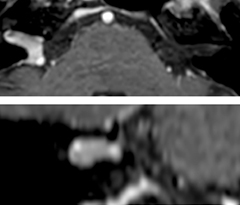

Excellent spine and spinal cord imaging

Looking for inflammatory lesions of the spinal cord is usually challenging with MRI, says Dr. Savatovsky. “We solved some of the challenges by implementing sequences such as 3D PSIR, which allows us to see far more lesions than the usual T2 imaging. We are starting to see cases where the MRI images at 1.5T were normal, but then we do see lesions when performing the PSIR at 3.0T.” [1]

“Elition also performs very well in imaging of the bony spine, the discs and degenerative disease, especially now that we can include at least one 3D sequence in every scan. For example, we perform a lot of 3D spin-echo (TSE) sequences when imaging degenerative lumbar spines. Thanks to Compressed SENSE and the 3D SpineVIEW protocols, we have a very high signal intensity with no flow voids, so the image quality is very good. The possibility to reformat the images in every plane raises the diagnostic confidence, especially in patients who have to undergo surgery.”